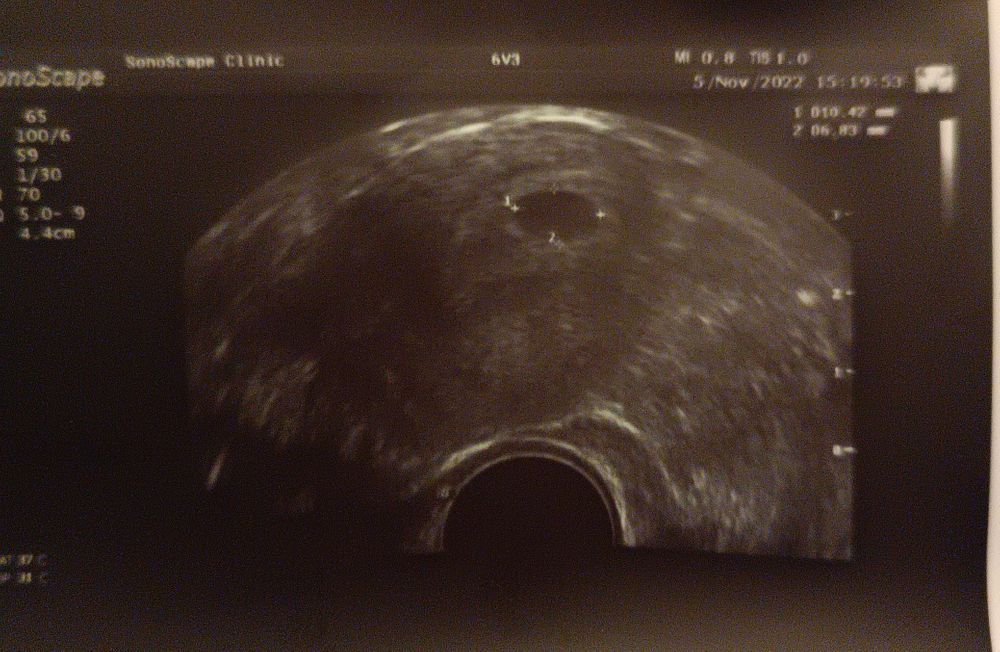

Первое УЗИ на 19 ДПП!

Я БЕРЕМЕННА !Ура! Сегодня Ре отдала мне вот такую фотку :)

ПЯ в матке ровно в том месте, где мы его и оставляли. Средний диаметр ПЯ - 8 мм.